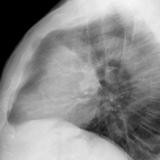

Case 8b Thymoma Lat